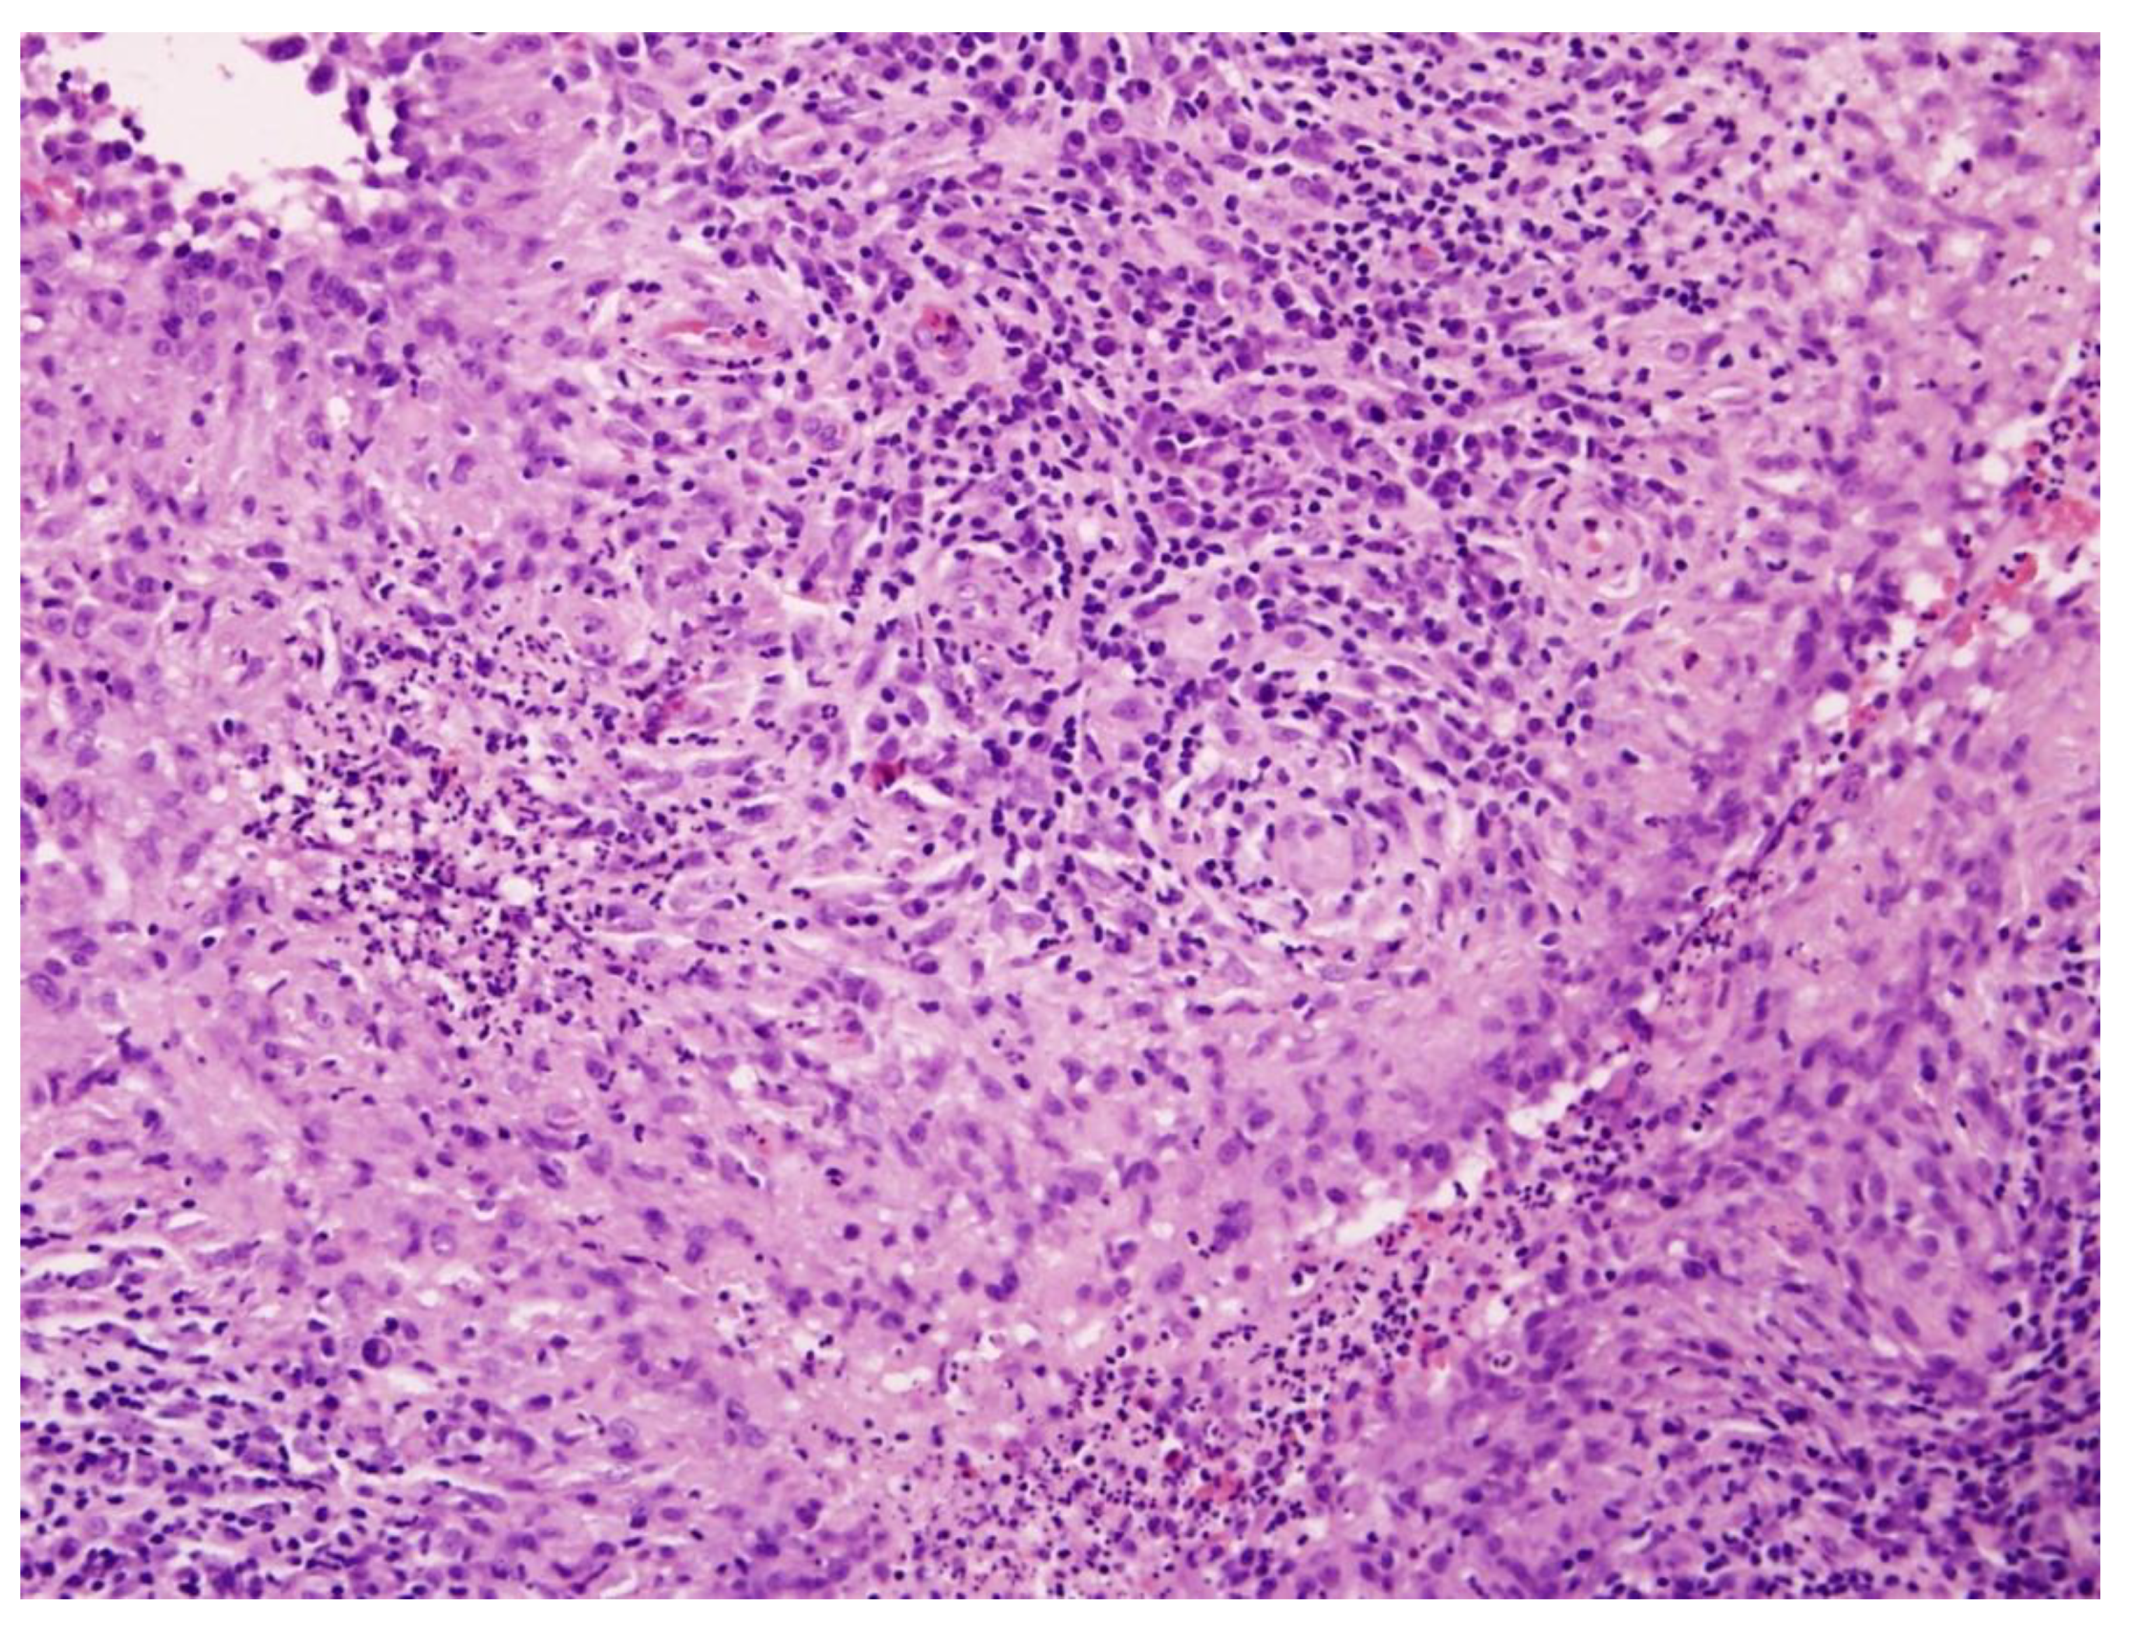

On admission, biopsies from the cheek and back were obtained. Histopathological examination of lesions revealed fragments of stratified squamous epithelium, possibly consistent with a ruptured epidermoid cyst, surrounded by a diffuse inflammatory infiltrate composed predominantly of lymphocytes, plasma cells, and histiocytes. Numerous palisading histiocytes formed granulomatous structures interspersed with scattered multinucleated Langhans-type giant cells. The dermis exhibited patchy fibrosis and areas of stromal homogenization, and involvement of the superficial subcutaneous tissue was evident. No caseation necrosis was present. The epidermis showed focal hyperkeratosis and acanthosis without evidence of epithelial dysplasia or malignant transformation. The histologic findings were consistent with, though not pathognomonic for, CTB (Figure 1). PCR confirmed the presence of M. tuberculosis DNA. Systemic evaluation was performed to assess for extracutaneous involvement. No clinical or radiologic evidence of pulmonary, lymph node, bone, or visceral tuberculosis was identified, and the disease was considered limited to the skin. A diagnosis of LV was made, and ATT (rifampicin 600 mg/day and isoniazid 300 mg/day) was initiated. The therapeutic regimen was prescribed following consultation with a tuberculosis specialist, with the choice of agents influenced by the patient’s concomitant medications and the potential drug interactions, and consisted of a 6-month course of combination therapy.

Figure 1.

Histopathological image of cutaneous tuberculosis (H&E staining, ×100). The dermis contains well-formed tuberculoid granulomas composed of epithelioid histiocytes and Langhans-type multinucleated giant cells, surrounded by dense lymphoplasmacytic infiltrate. Caseation necrosis is absent, consistent with LV.